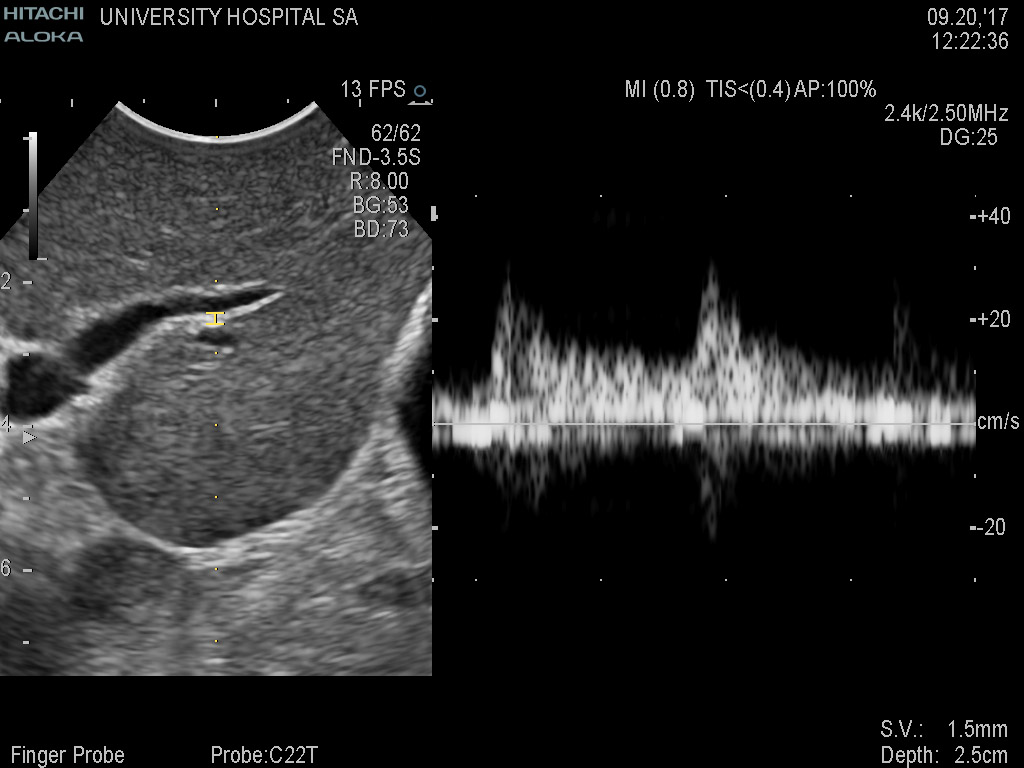

Superior guidance for all applications

Fujifilm Healthcare Americas is committed to designing tools that help surgeons navigate inside the human body and provide the necessary information to immediately make critical surgical decisions.

Fujifilm Healthcare's dedication to Surgeons provides outstanding ultrasound technology, professional support and the specialized tools necessary to best perform comprehensive real-time ultrasound imaging in Breast Surgery, General Surgery, Laparoscopic Surgery, Neurosurgery, Robotic Surgery and Surgical Oncology.

Fujifilm Healthcare’s ARIETTA Precision features state-of-the-art digital architecture and advanced imaging technologies to redefine the capabilities of surgical ultrasound.

Imaging Clearly Defined

State-of-the-art digital architecture and advanced imaging features to redefine the capabilities of surgical ultrasound.